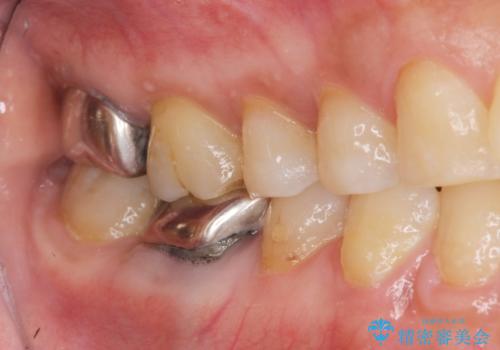

- 他院で虫歯が大きすぎて歯を抜くしかないと言われ、歯を残す手段はないものかと当院へ初診来院されました。

#17は失活歯で歯肉方向への縁下カリエス、#16は生活歯であるものの歯髄ギリギリの処置となるであろうとが予想される治療です。

歯周外科、マイクロスコープを用いた虫歯治療を行い歯を残す治療計画を立てます。